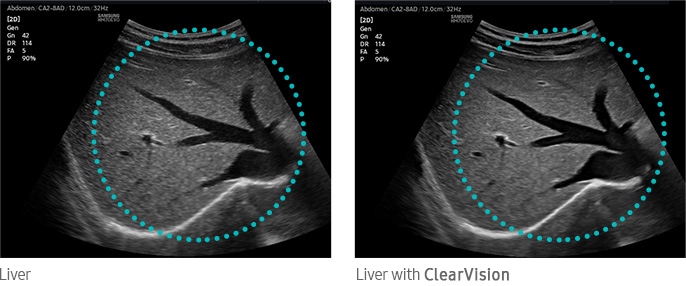

Noise reduction filter to improve 2D image quality

The noise reduction filter improves edge enhancement and creates sharp 2D images for optimal diagnostic performance. In addition, ClearVision provides application-specific optimization and advanced temporal resolution in live scan mode.

Liver with ClearVision